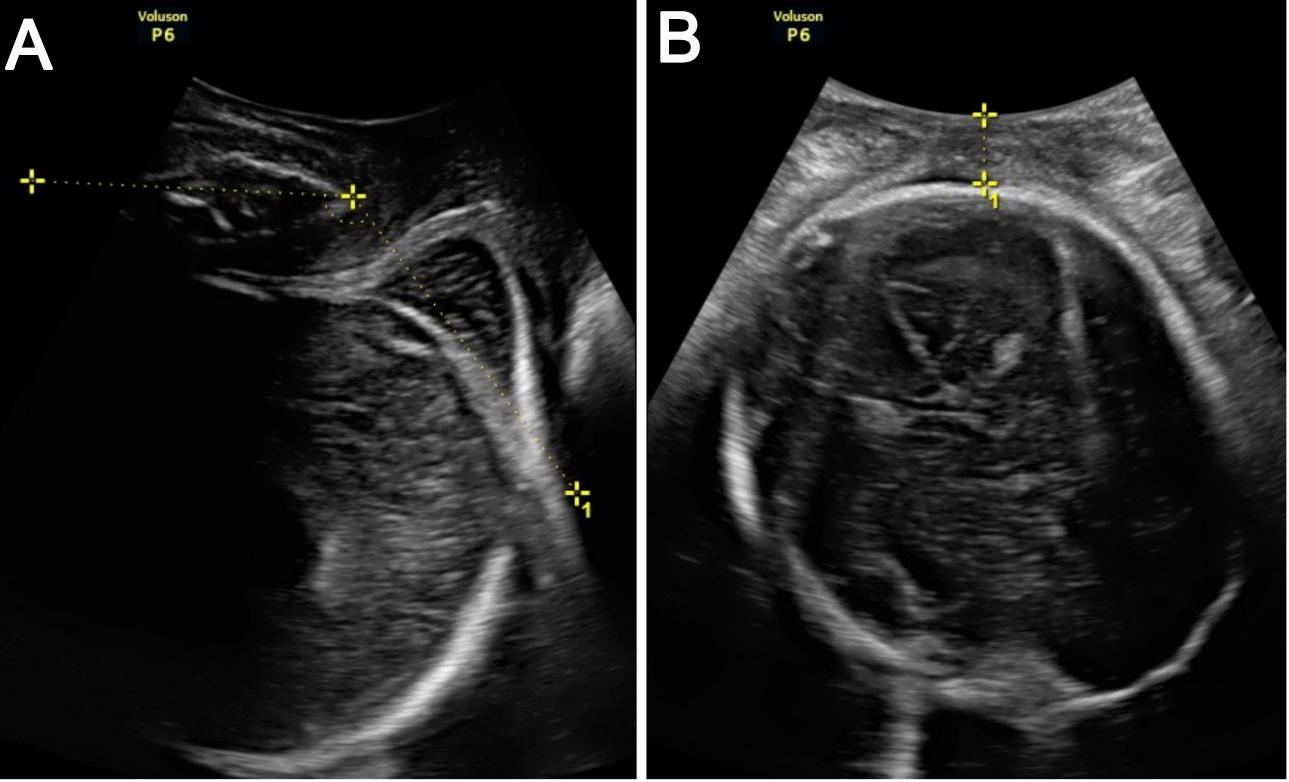

Secondly, the measurement of the AOP in the midsagittal plane was performed. Small lateral and anteroposterior movements of the probe were required for obtaining a clear sagittal view with clear maternal pelvic (pubic symphysis) and fetal (fetal skull) landmarks. The AOP was measured as the angle between the long axis of the pubic bone and a line from the anterior border of the pubis drawn tangentially to the deepest bony part of the fetal skull (Fig. 2).

Fig. 2.ITU measurements in maternal lateral position. (A) Measurement of the AOP in the midsagittal plane (the AOP is the angle between the long axis of the pubic bone and a line from the anterior edge of the pubis drawn tangential to the deepest bony part of the fetal skull). (B) Measurement of the HPD in the frontal plane (the HPD is the shortest distance from the outer bony limit of the fetal skull to the perineum).

Thirdly, back to the frontal plane, the HPD was measured. The HPD was measured as the shortest distance from the outer bony limit of the fetal skull to the perineum (Fig. 2).